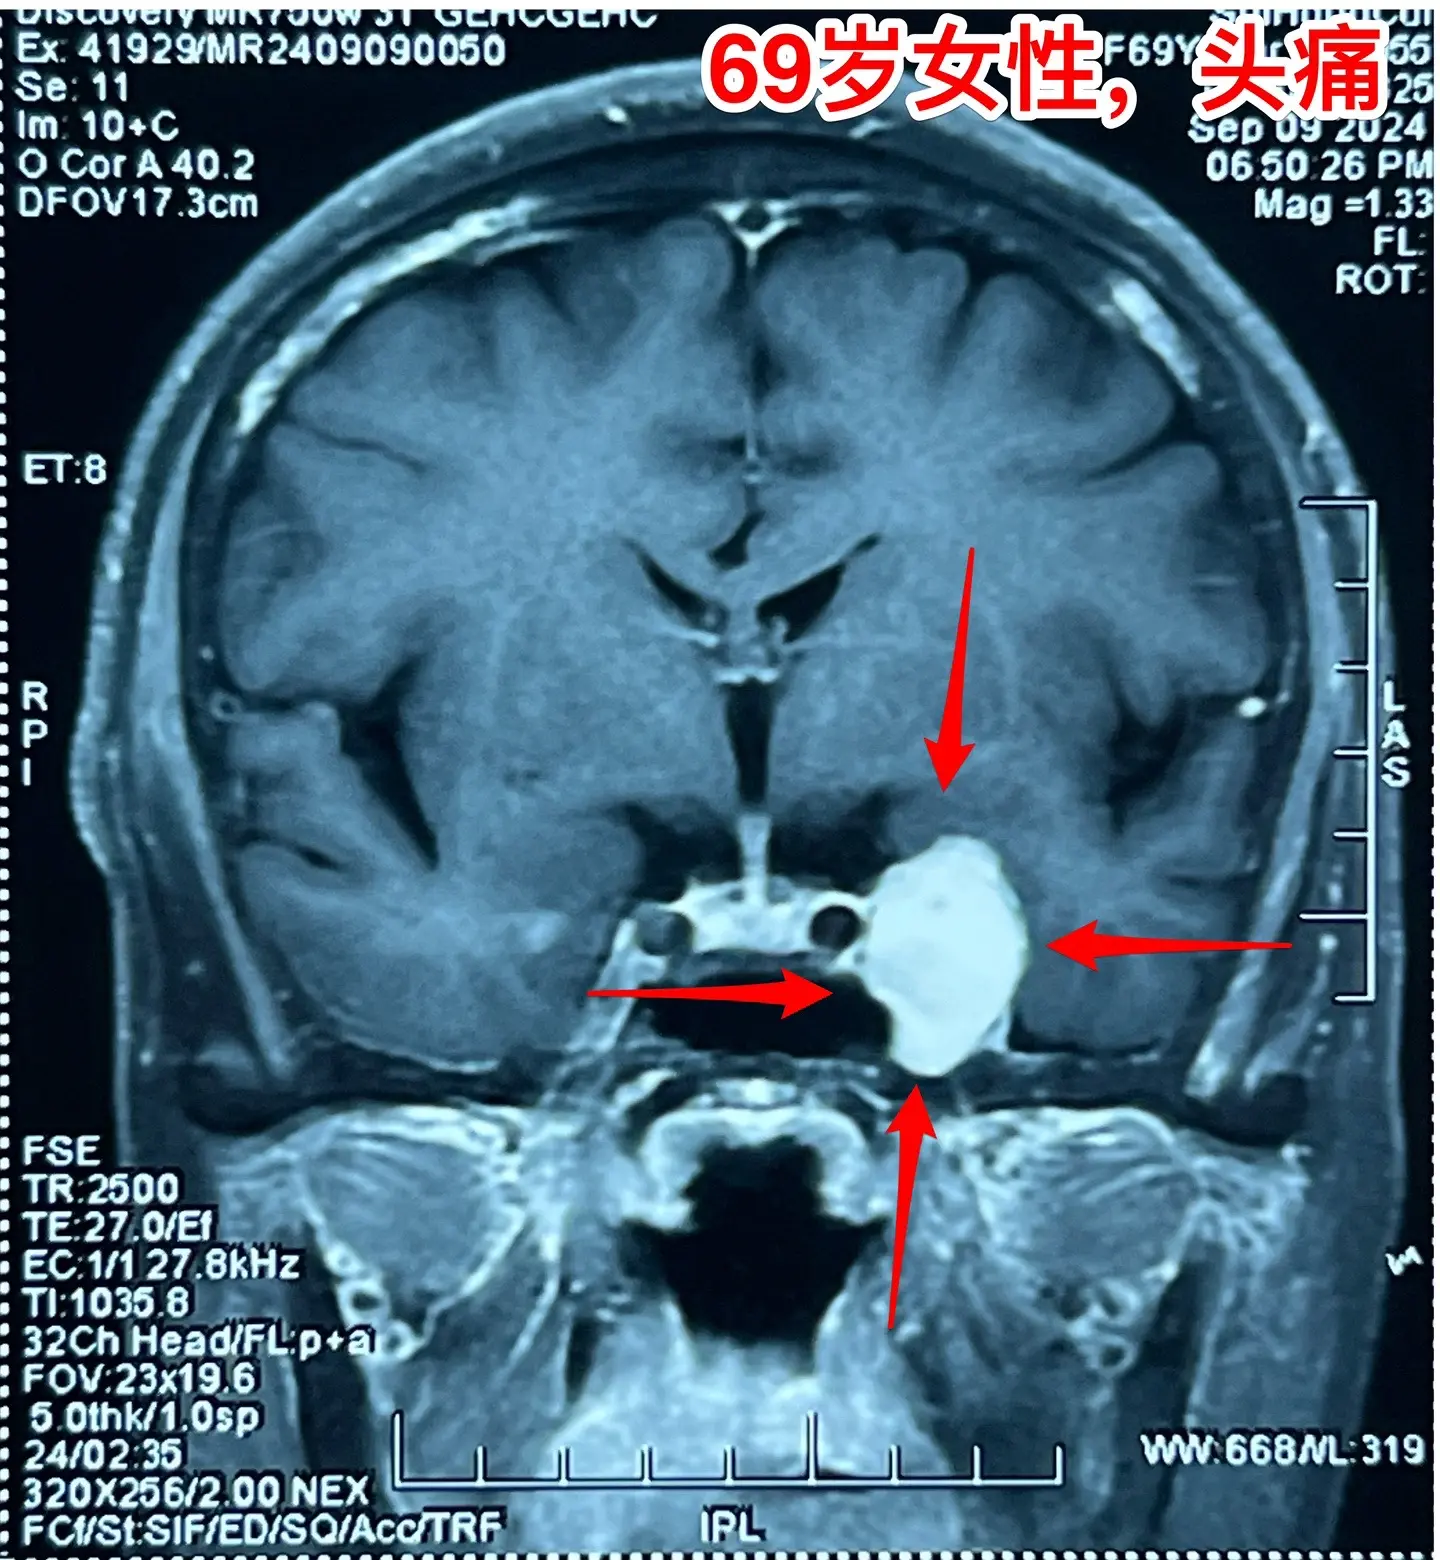

海绵窦区神经鞘瘤,是良性肿瘤。69岁青岛市老太太经常感到头痛,不太剧烈...